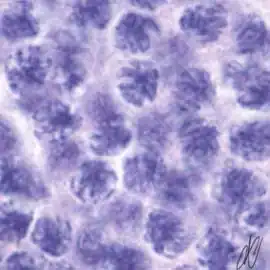

spermatogenesiscysts with successive stages of spermatogenesis in a seminiferous tubule | |||

| H&E | Putt's carbol fuchsin as a marker of spermatogenic maturation |